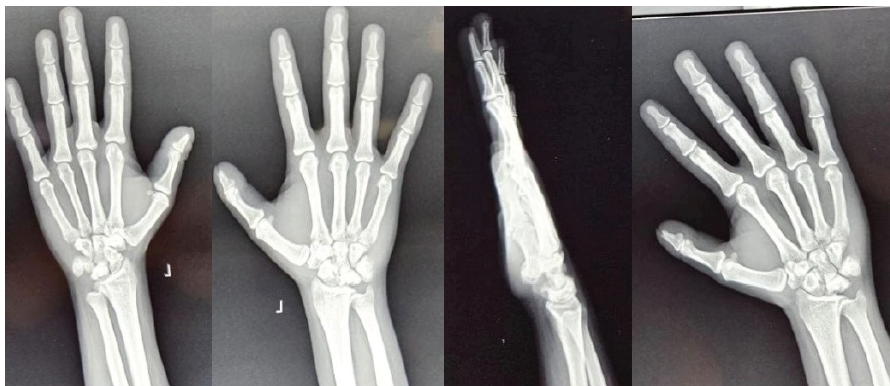

A representative example of Case 1 is illustrated in Figures 1–6. The preoperative radiograph is shown in Figure 1, while Figure 2 demonstrates the MRI findings confirming avascular necrosis of the lunate. Figures 3–5 depict the immediate postoperative radiographs and sequential follow-up images up to 1 year. Figure 6 shows the final clinical photograph, demonstrating a good functional outcome.

Figure 1: This is an example of case 1, which shows a pre-operative image of anteroposterior, oblique, and lateral radiographs revealed lunate sclerosis, cystic changes, and coronal plane collapse, consistent with Lichtman stage IIIA.